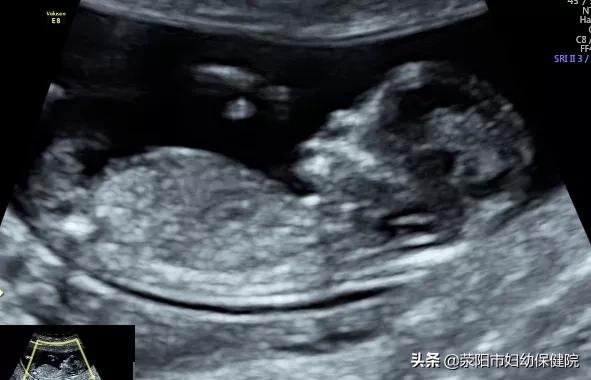

1.NT检查:

NT检查是检查胎儿颈项透明层,排查唐氏综合征的重要检查之一,建议不能省略。一般筛查的时间在11-14周,孕产妇可以根据自己的孕周时间延后,最晚不能超过14周。

3.大排畸:

也就是在22-24周要做的四维彩超。这段时间胎儿大小和羊水适中,是筛查胎儿畸形的最好时期,孕妇们不要轻忽,可以合理安排时间,赶在24周之前去做。